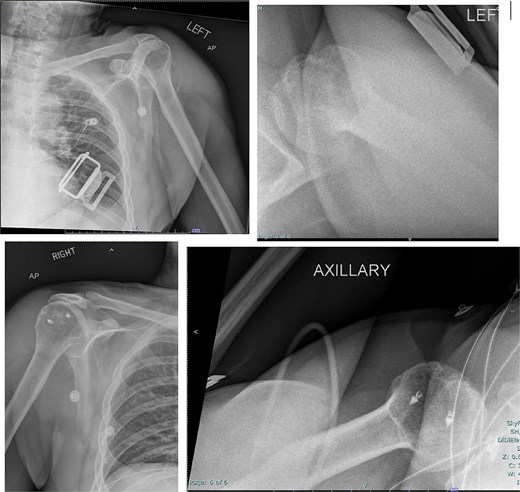

Both shoulders were reduced urgently by the orthopedic team, with immediate improvement in paresthesias (Fig. 2). Post-reduction CTs were significant for bilateral chronic rotator cuff disease with superior migration of the humeral heads, right-sided supraspinatus and subscapularis atrophy, and a left nondisplaced glenoid fracture (Figs 3 and 4). He was discharged home in bilateral slings.

Post-reduction X-rays demonstrating congruency restored to right and left glenohumeral joints, with evidence of superior humeral head migration bilaterally.